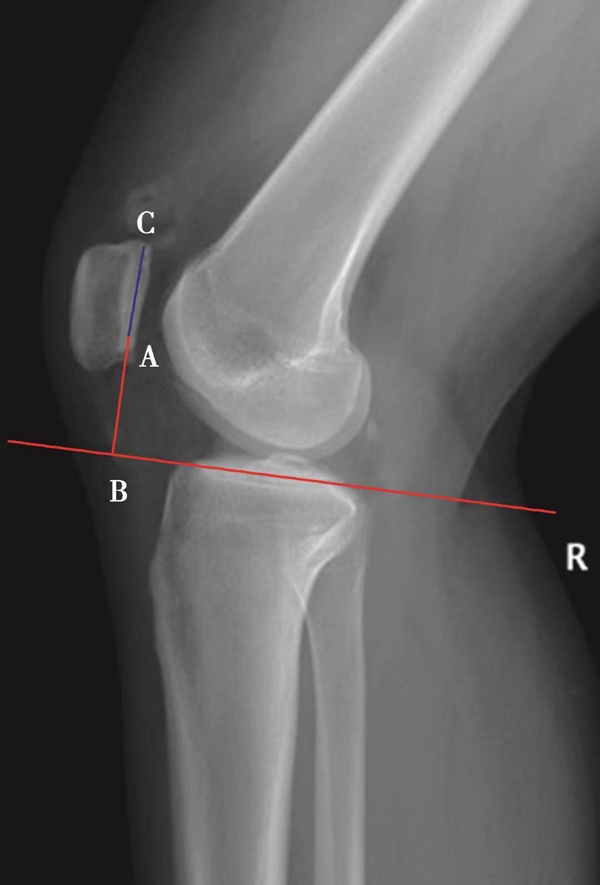

如图示:AB是髌韧带长度,AC髌骨纵轴长度。Insall-Salvati指数=AB/AC(图4)。

图3 Caton指数=AB/AC=1.30,为高位髌骨

图4 Insall-Salvati指数 =AB/AC=1.10,为正常髌骨高度

图5 Insall-Salvati指数=AB/AC=1.40,为高位髌骨

但是此法测量髌骨韧带时往往依赖准确的估计胫骨结节与髌骨下极的位置。因此,髌骨下极和胫骨结节的病变都会影响测量的结果,尤其是发生胫骨结节骨软骨炎的患者确定这一位置便更加的困难。此外,该指数不能用于评估胫骨结节向近端或远端移位的效果。因为该指数测量所使用的标记在胫骨结节术后均未发生改变,Insall指数也就不会变化。